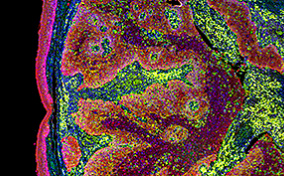

Imaging Tests Play a Significant Role in Detecting Testicular Cancer

So you have a lump. Your medical team will likely use diagnostic images to investigate.